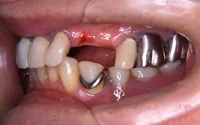

■治療前:奥歯が無いため噛み合わせが深く下の歯が全く見えない

噛み合わせが低いため全体的に歯が削れている

| 主訴 | 歯科治療をしても歯がすぐに欠けてしまう 奥歯が無いため、奥歯で咬めない |

| 治療方法 | インプラント治療 + 補綴治療 |

| 治療期間 | 約1年 |

| 通院回数等 | 約20回 |

| 費用 | 約250万円(税込) |

| リスク・副作用 | 術後の腫れ・痛み |